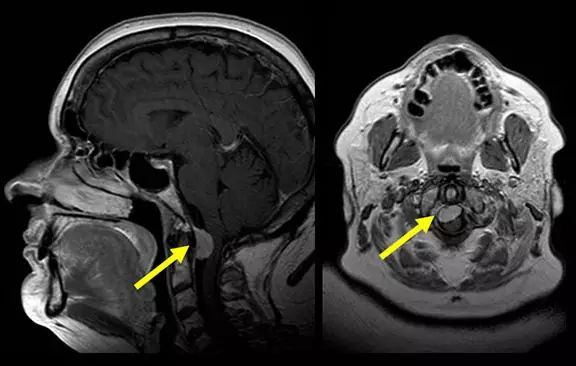

发生在颅颈交界部的脑膜瘤(MRI扫描,矢状位[左]和轴位[右])称为枕骨大孔脑膜瘤。枕骨大孔区肿瘤的经典表现包括肢体无力、感觉改变,无力症状开始于同侧臂,然后进展到同侧腿,之后是对侧腿,对侧臂。检查发现,患者触觉正常,但病灶对侧痛觉和温度觉缺失。往往上肢位置和振动感觉缺失比下肢严重。